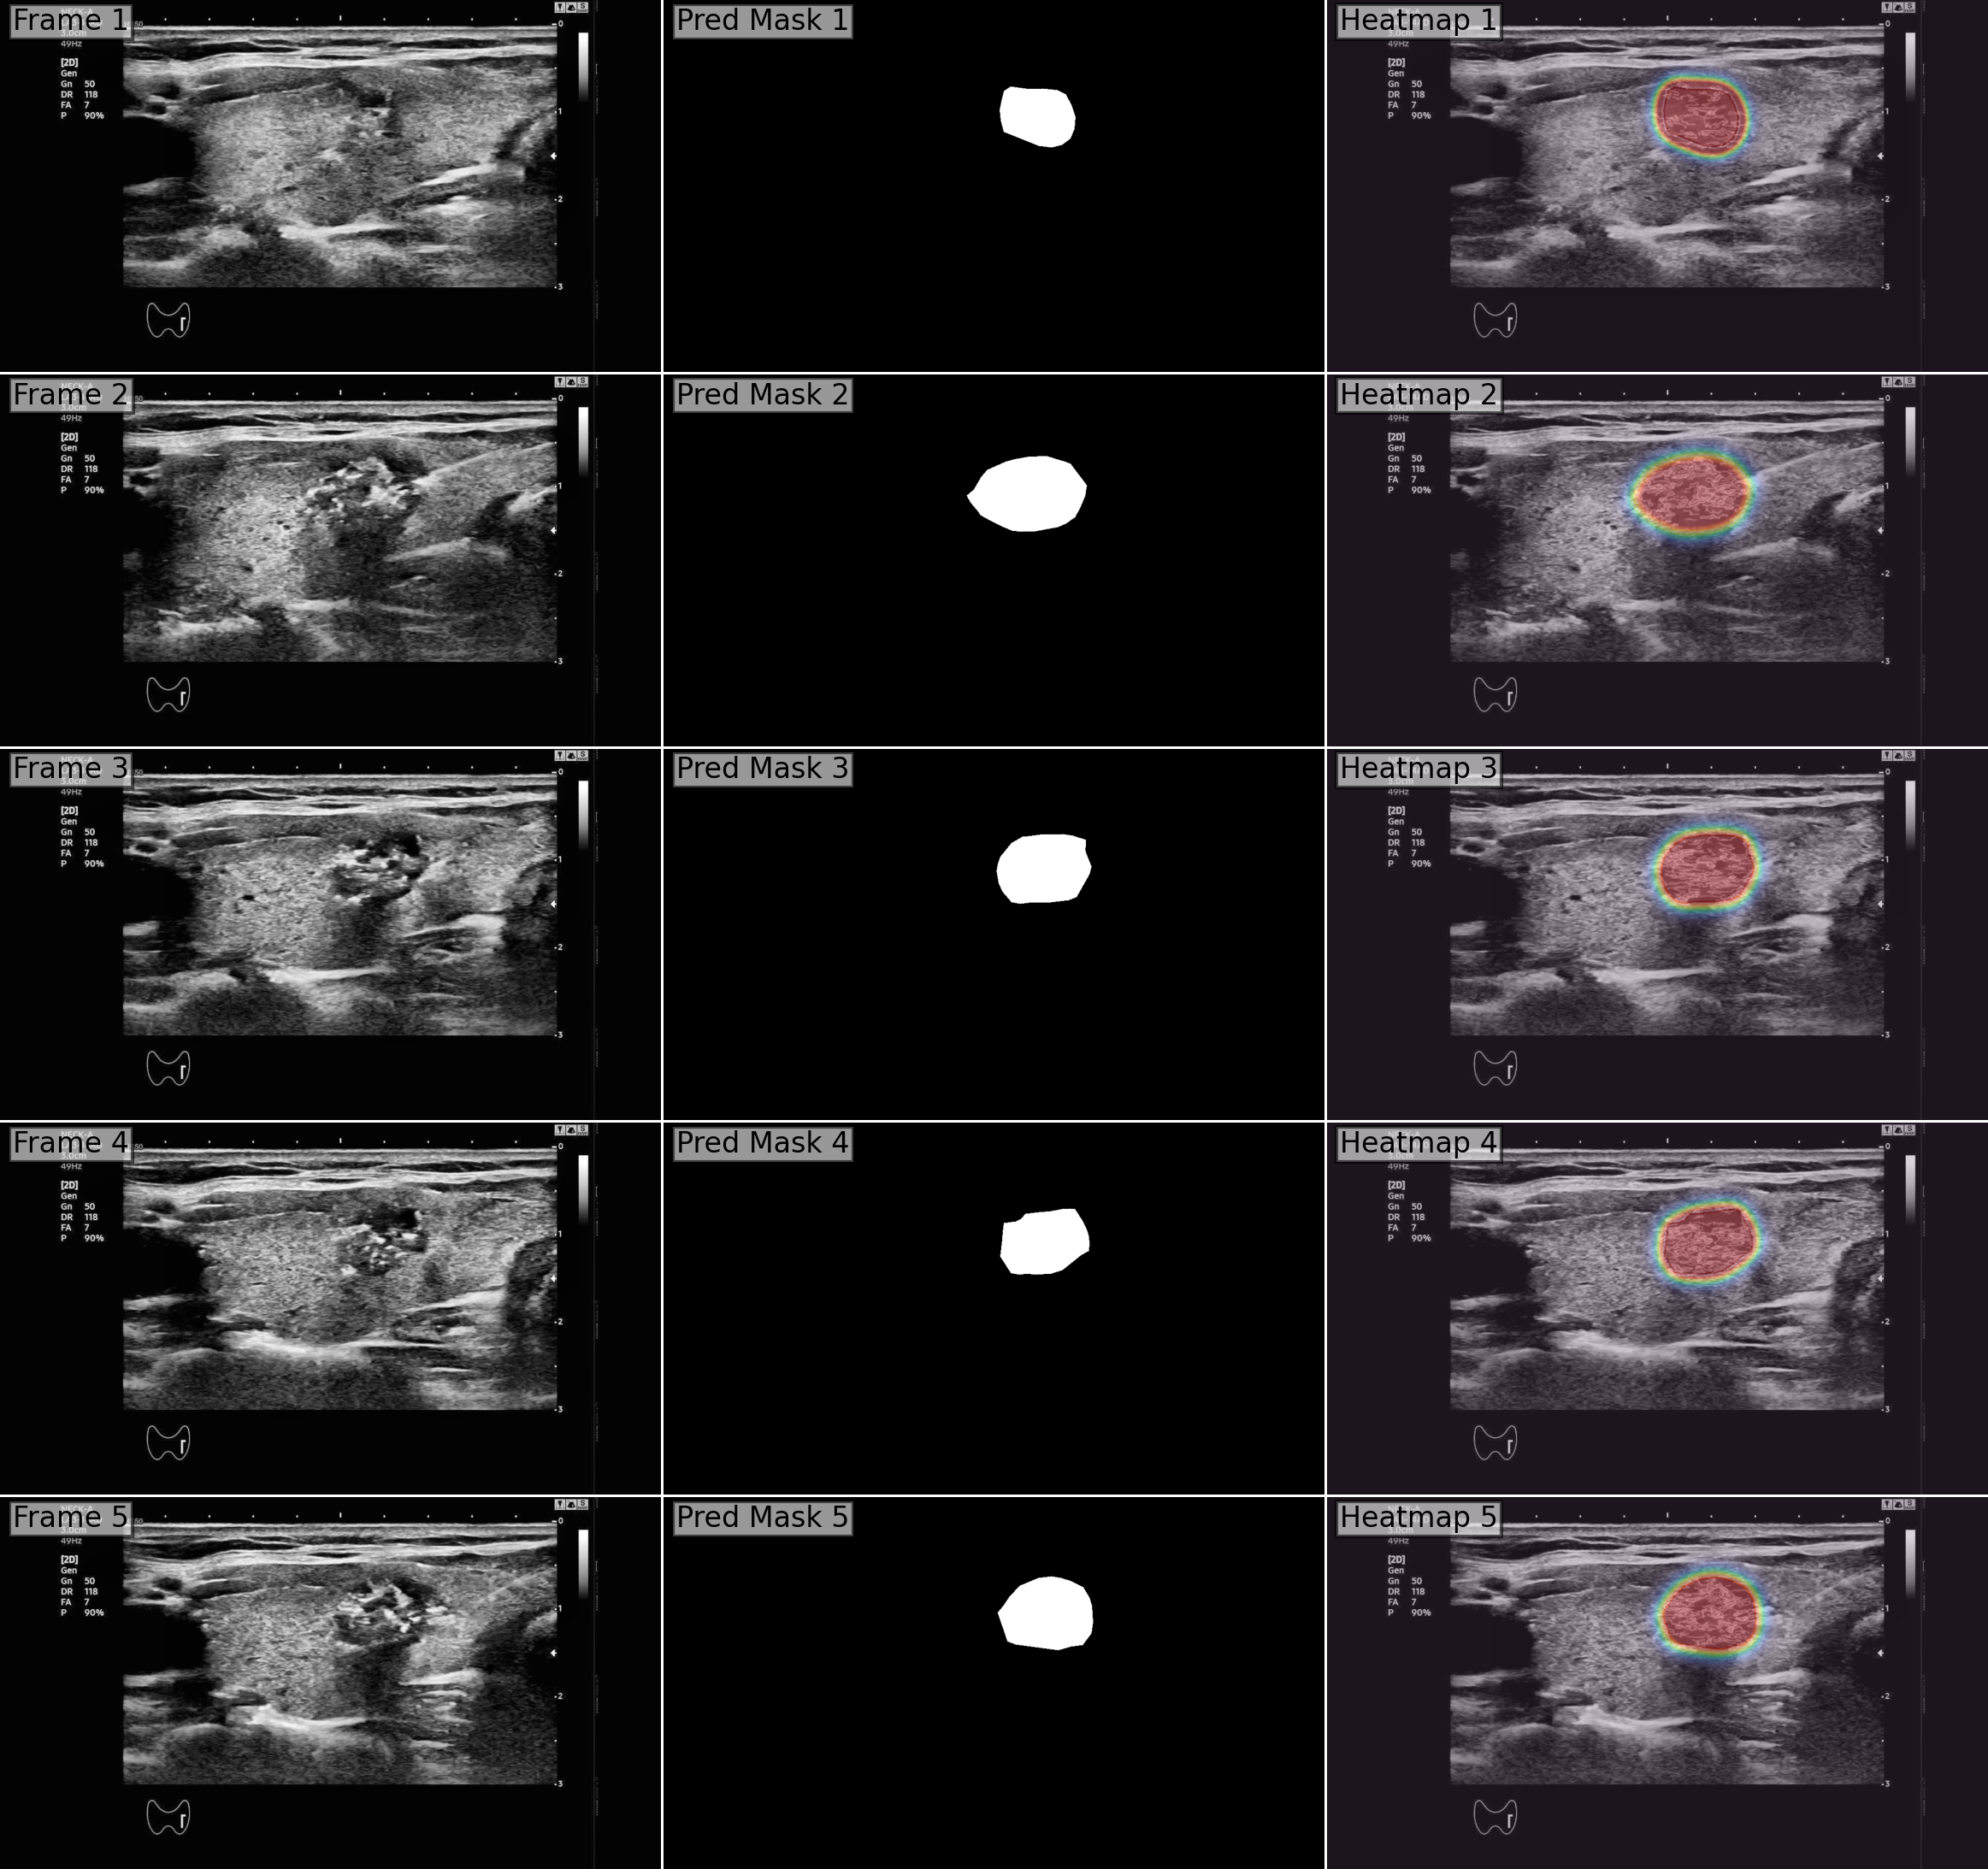

To interpret how EMA-SAM maintains stable tumour tracking during ultrasound-guided RFA, we applied Grad-CAM++ [28] to consecutive frames and visualized the resulting heatmaps (Figure 3). Unlike raw segmentation masks, which provide only binary lesion boundaries, these gradient-based maps expose the internal reasoning of the network by highlighting image regions most influential to its predictions. The results demonstrate that the model consistently concentrates attention on the PTMC lesion itself, even when probe pressure alters tissue appearance or when heat-induced micro-bubbles create partial occlusions. Importantly, the heatmaps confirm that EMA-SAM does not drift toward irrelevant structures, validating that the exponential-moving-average pointer stabilizes the latent tumour representation while still permitting rapid re-alignment once high-confidence evidence reappears.

Across ultrasound-guided RFA videos, EMA-SAM improves both segmentation accuracy and temporal robustness relative to SAM-2 while preserving real-time throughput. On our PTMC-RFA dataset (Table 1), EMA-SAM raises maxDice from 0.82 to 0.86 ( +0.04 ) and maxIoU from 0.72 to 0.76 ( +0.04 ), alongside consistent gains in (0.910.94), (0.940.96), and a reduced MAE (0.0190.015). Qualitatively (Fig. LABEL:fig:sam2_ema_closely_packed), EMA-SAM maintains coherent tumour outlines through probe motion and bubble-induced occlusion, whereas SAM-2 exhibits flicker or transient drift. Grad-CAM++ visualizations (Fig. 3) further show that EMA-SAM concentrates attention on the lesion and avoids spurious regions during challenging frames.